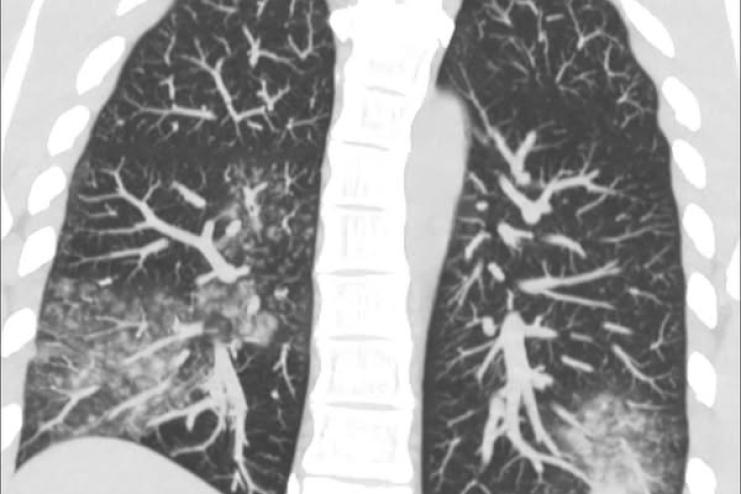

Метапневмовірус — це звичний вірус, який циркулює в Україні протягом кожного епідсезону. Його симптоми зазвичай нагадують легкі прояви застуди чи грипу, зокрема:

На відміну від грипу, це захворювання в більшості випадків протікає легко й рідко викликає ускладнення.